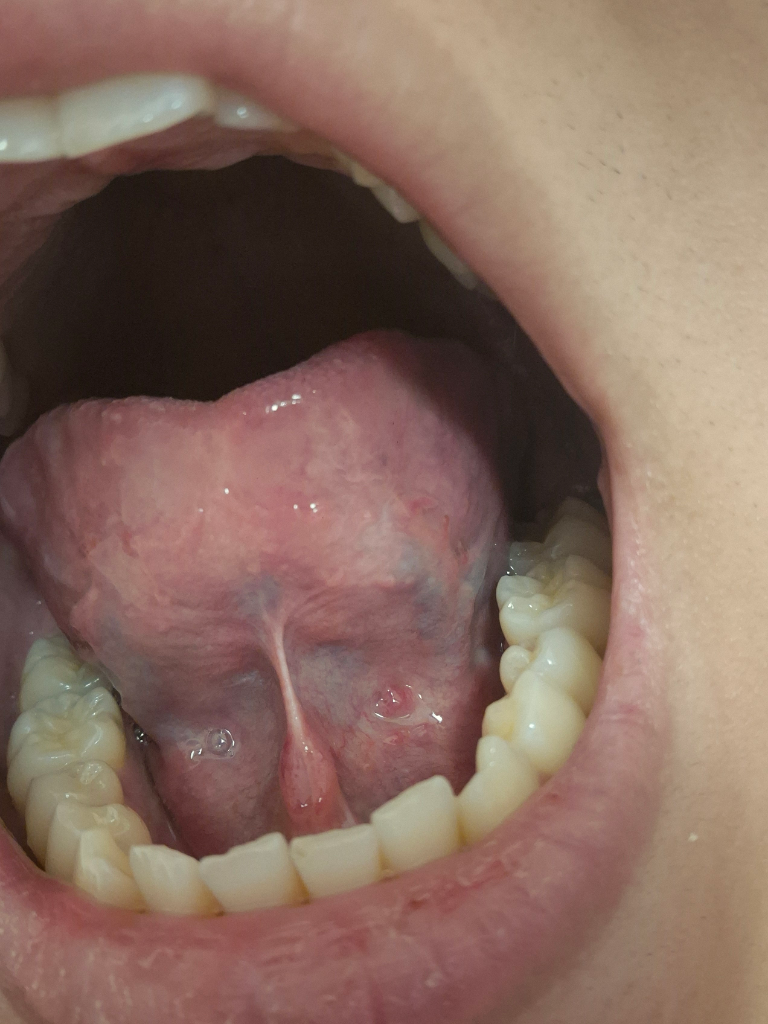

혹시 혀밑에 붉은 점과 같은 것이 구강암입니까

구강암이 아니면 다른 질병이 있는지도 확인이 가능합니까 평상시에는 보이지 않다가 오늘 보니까 확인이 되었습니다. 부탁드립니다.

유감스럽지만 해당 사진들만 가지고 구체적으로 구강 암이나 다른 구강 내부의 질병을 감별할 수 없습니다. 우려스러우시다면 이비인후과적으로 진료 및 조직 검사 같은 정밀검사를 통해서 파악을 해보아야 하겠습니다.